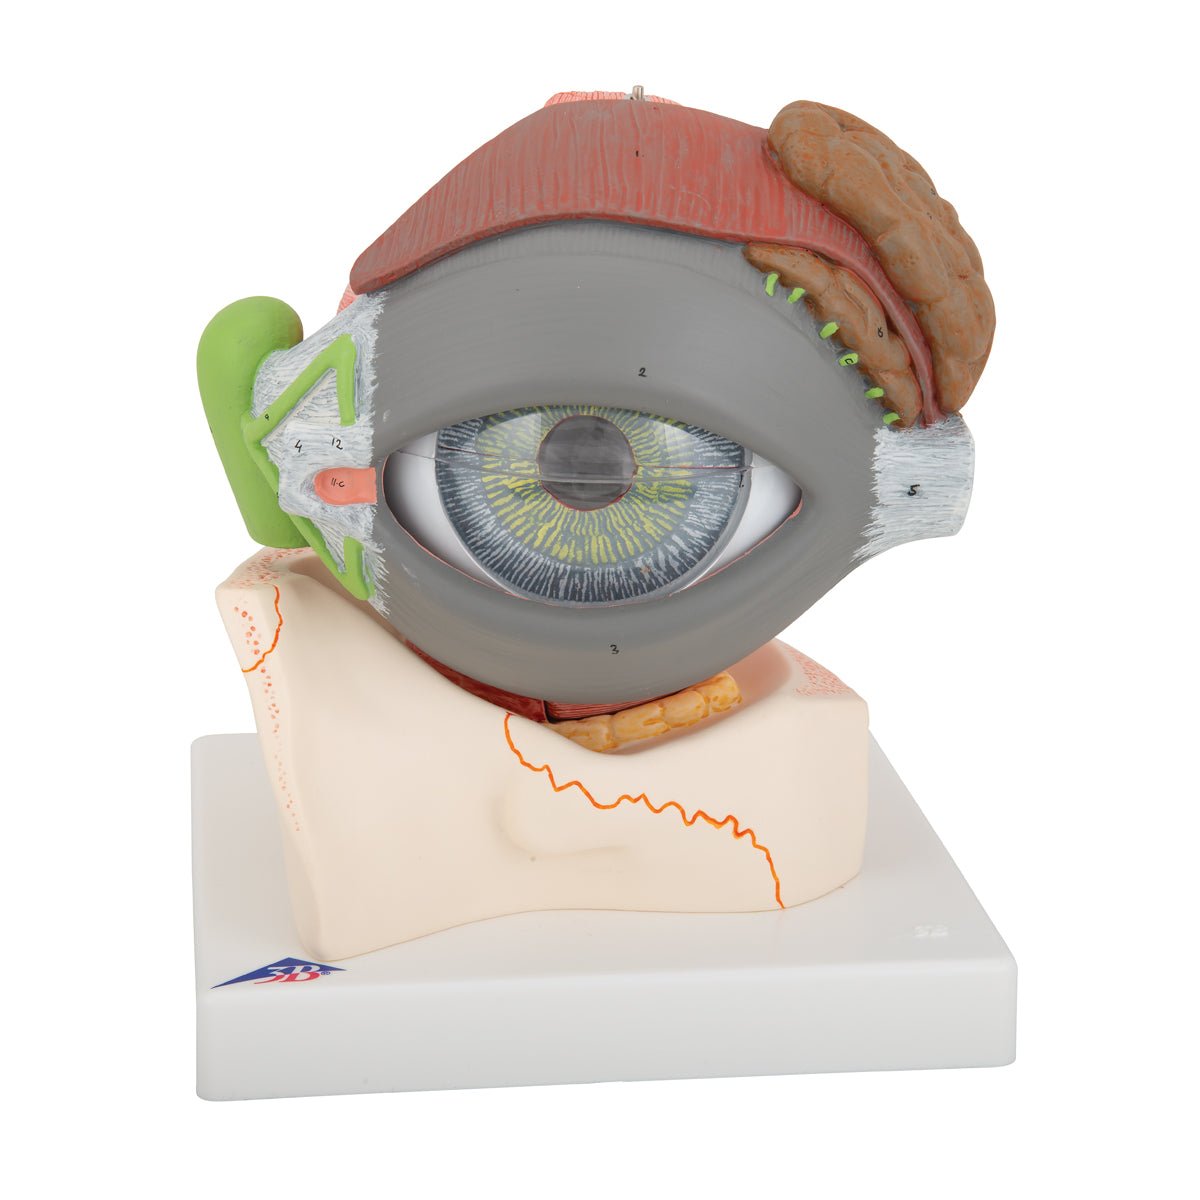

Selling anatomical models is the mainstay of eAnatomi, although we also spend a lot of resources developing our own anatomical materials such as posters. Anatomical models are used for various purposes and can show both defined tissues, organs and organ systems. Are you looking for a simple model of bone tissue or perhaps an advanced torso model based on MRI technology, you can find it all at eanatomi.com.